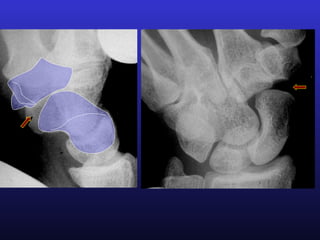

Anterior midcarpal clunking

 The ligaments mostly involved in the palmar midcarpal

instability are the scaphotrapezial ligament, and the

triquetrum-capitate-hamate ligament.

 The proximal row remains tilted palmarly until near the

end of ulnar deviation, where it suddenly rotates into

25º

extension, sometimes with a palpable thud (catch-up

RADIOLUNATE ANGLE

clunk).

 In most cases there is a combination of medial and lateral

ligament insufficiency.

0º                           Clunk !

 There are cases where the dysfunction clearly derives

from a predominant injury at the scaphotrapezial ligament

(anterolateral midcarpal instability) or from a

predominant injury ot the triquetrum-capitate-hamate

-25º

ligament (anteromedial midcarpal instability). Stress

views are recommended to assess the location of the

Radial dev   Neutral      Ulnar dev

predominant injury.

CLUNK